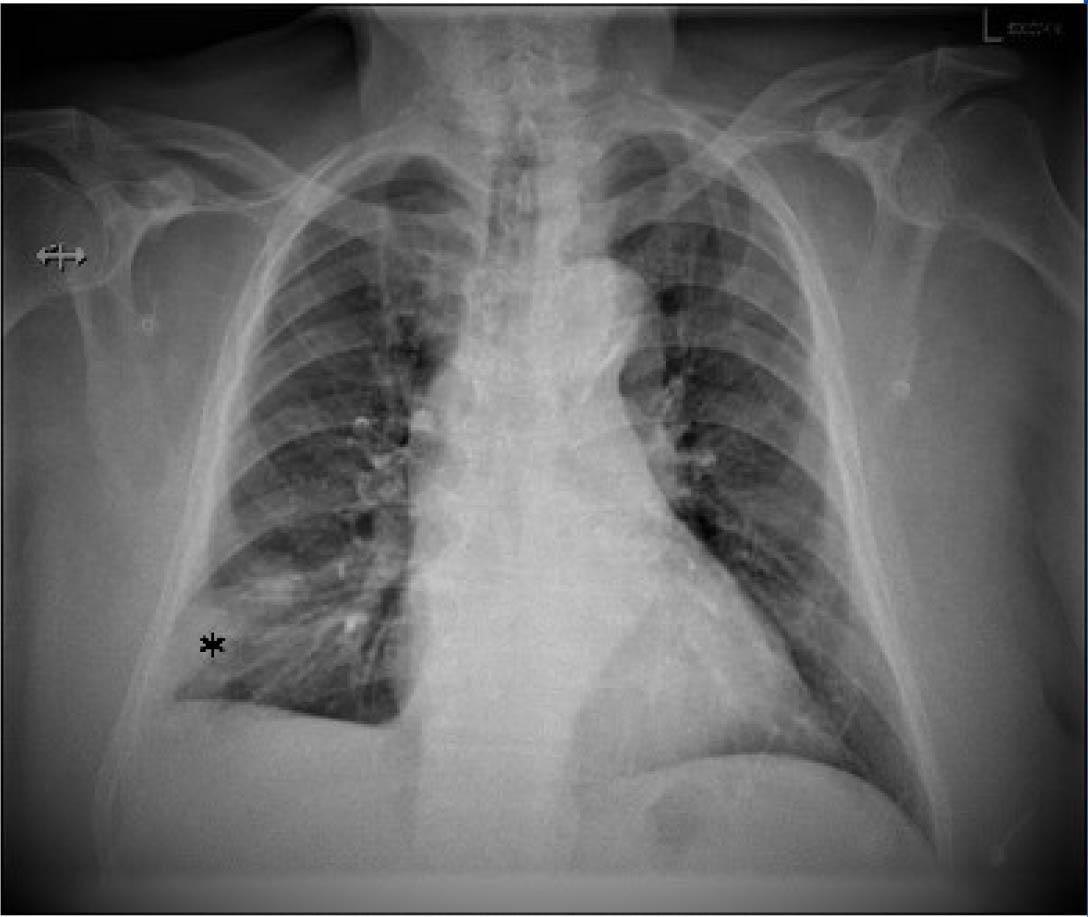

Figure 3

Chest x-ray that shows right lower lobe condensation opacity, without aerial bronchogram suggestive of pulmonary infarct.